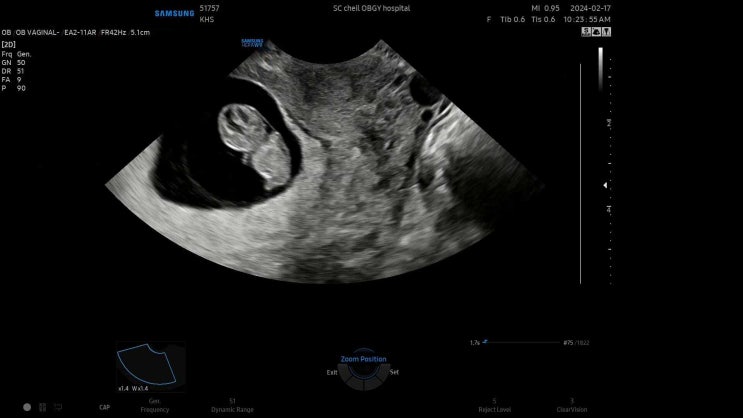

6주차, 난황 안녕! (태아보험가입과 산후조리원 계약까지)

일주일 만에 다시 병원을 방문했다. 비어있는 아기집이 자꾸 아른거렸고 심장소리도 듣고 싶고 괜히 걱정할...